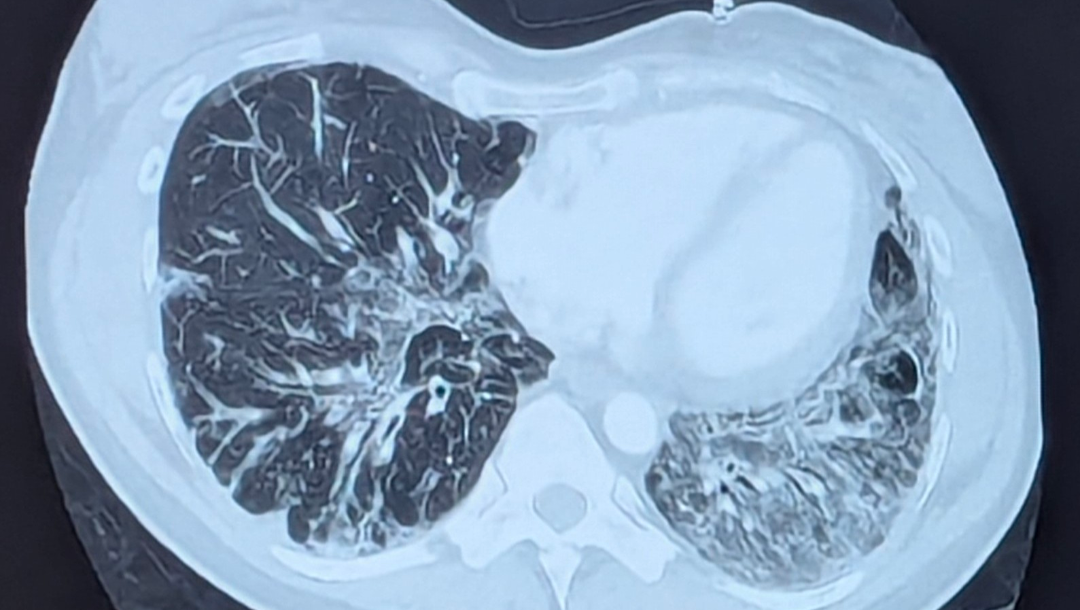

The photo I have included shows the CT scan of my lungs. All the white you see is the scar tissue.

Right before Christmas, I got sick with COVID, which turned into double pneumonia. I was not getting any better after weeks of being sick. I went back to the emergency room, and they admitted me. After 2 CT scans and a ton of other tests, they thought I had pulmonary fibrosis. However, this may not be the case.